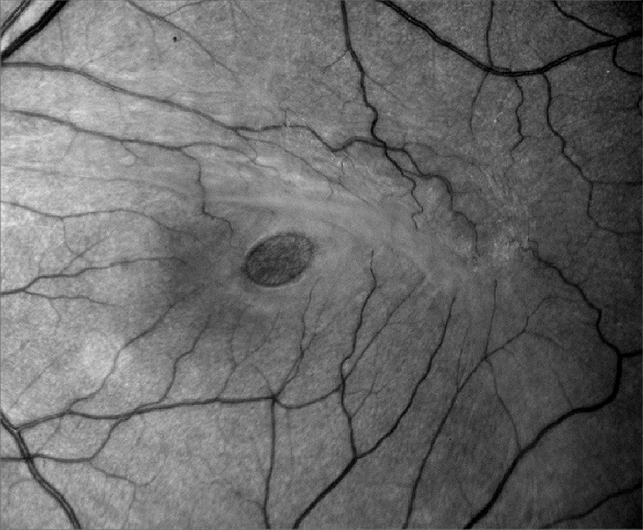

Сквозной макулярный разрыв, обнаруженный при помощи прямой офтальмоскопии, характеризуется четко выраженным повреждением в макуле круглой или овальной формы с желто-белыми скоплениями в основании. Эти желтые точки, вероятно, представляют собой заполненные липофусцином макрофаги или узелковые образования основного пигментного эпителия со скоплением эозинофилов. При биомикроскопическом осмотре, при котором используют четко направленный луч света, хорошо видно округлое углубление с четко очерченными краями. У большиства пациентов над углублением можно наблюдать полупрозрачные ткани, образующие псевдомембрану. Вокруг углубления обычно собирается субретинальная жидкость. По краям разрыва можно также наблюдать кистовидные изенения сетчатки. Пигментный эпителий сетчатки обычно не претерпевает изменений в острый период, однако со временем он может быть подвержен хроническим изменениям, таким как атрофия и гиперплазия. Под эпиретинальной мембраной может наблюдаться нежное сморщивание внутренних слоёв сетчатки, которое иногда даже может маскировать разрыв.

Наиболее точной диагностикой для определения сквозных макулярных разрывов и отличия их от других видов повреждений являются тест Вотцке-Аллен и лазерная световая диагностика.